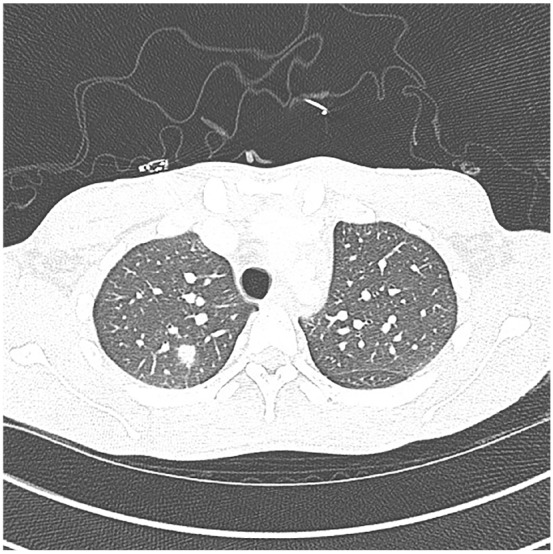

Although extrapulmonary Coccidioides infection is rare, it has been shown to disseminate to the skin and musculoskeletal system, with a strong affinity for bone. We present a case of disseminated Coccidioides infection with bone scintigraphy indicating diffuse fungemia despite equivocal serum assay, leading to appropriate antifungal therapy and a full recovery.